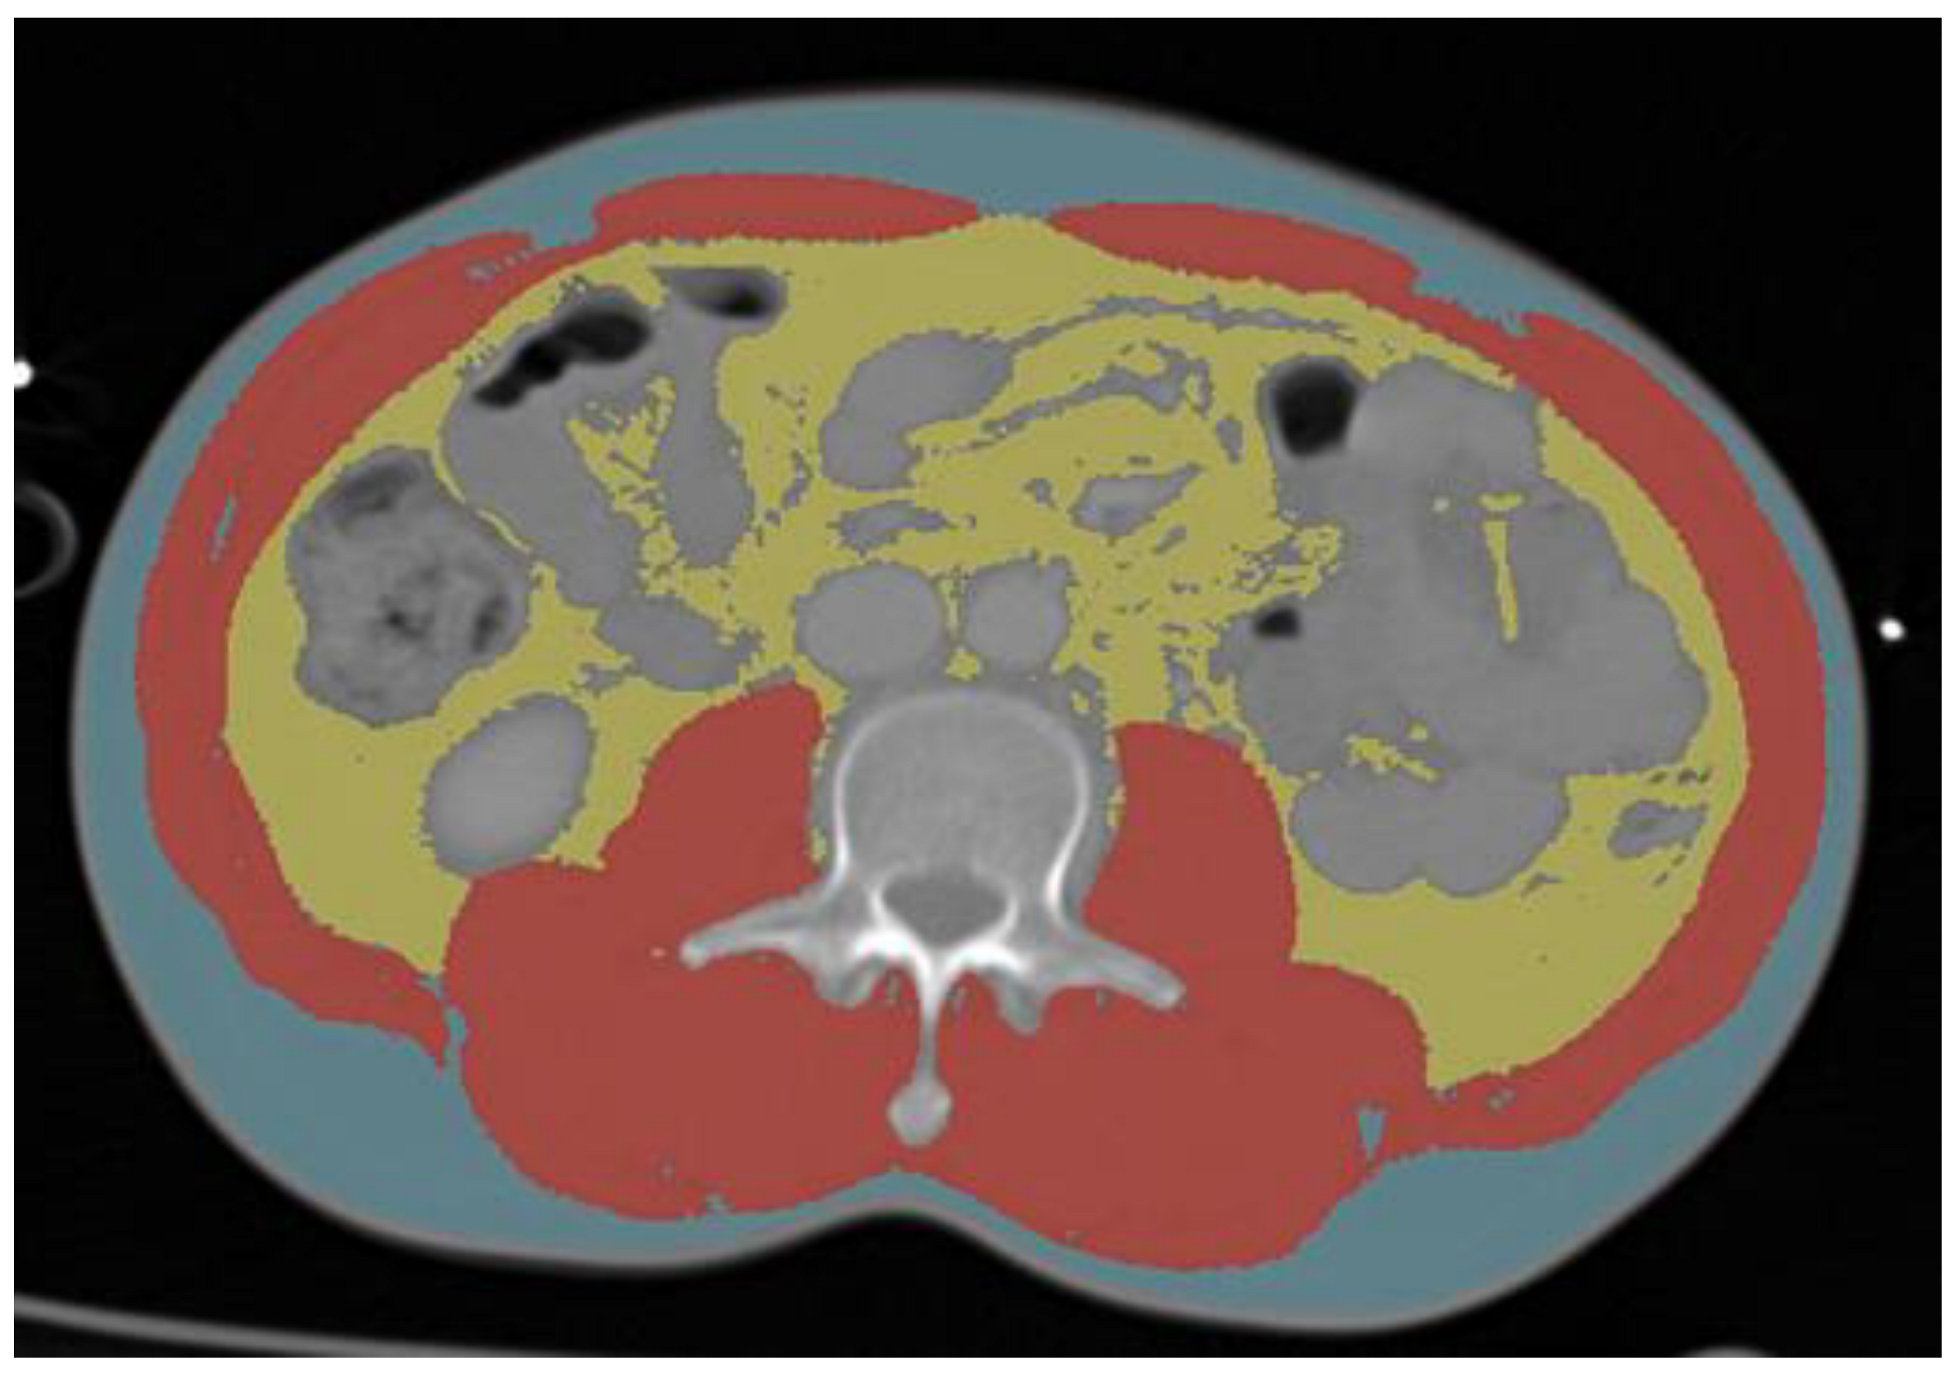

2.6. BC Analysis Using CT